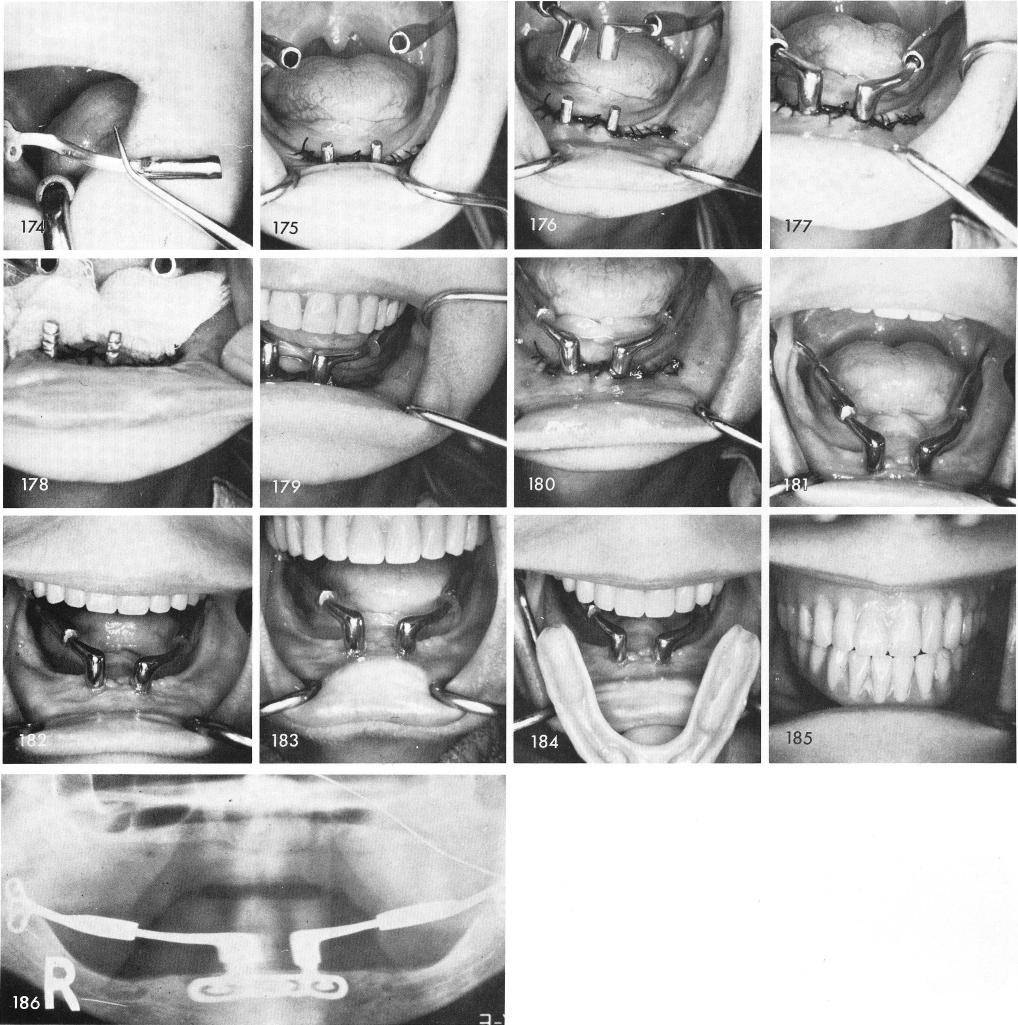

posts, figs. 176, 177, then removed so the various parts could be dried thoroughly, fig. 178, and cemented into position, figs. 179, 180. Figs. 181, 182, 183 reveals the healing.

The denture is adjusted and cemented with Duralay, figs. 184, 185. Fig. 186 shows the post-operative x-ray.

1 Post operative xray of the symphyseal ramus system